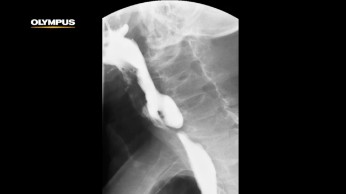

With the remarkable ability to enable en bloc resection of lesions throughout the gastrointestinal tract, ESD represents a major milestone in this evolution. It offers a potential alternative for open surgery when treating larger lesions. It also has revolutionized the treatment for early gastric cancers, becoming the preferred modality worldwide.1

ESD allows for the removal of the entire tumor or lesion in one piece, leaving the native organ esophagus and stomach intact. It often enables a return to normal function, and in the case of achalasia, patients regain their ability to swallow. Patients typically experience shorter hospital stays, faster recoveries, reduced pain and less expense after ESD compared to open or laparoscopic surgical procedures.2,3,4,5